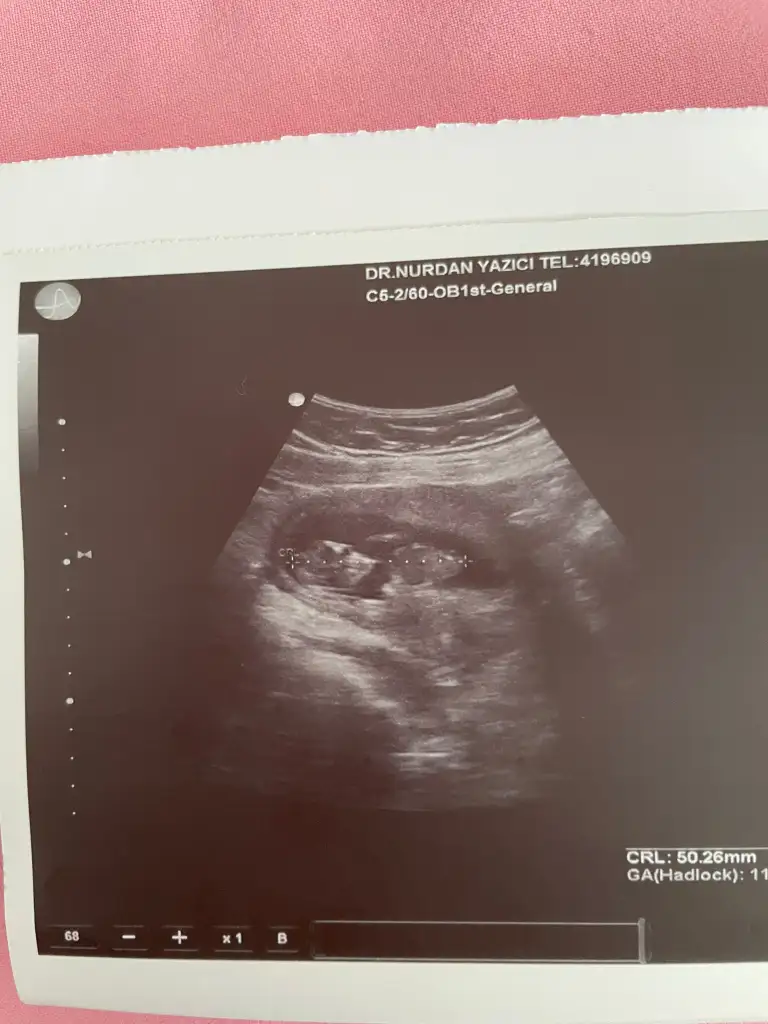

Bacaklarını toplamış o yüzden pek gözükmüyor 10 haftalık bir görüntüsü var vajinal daha net gibi atayım bakınUltroson fotoğrafından pek belli olmuyor sizin genelde nub teorisi doğru çıkıyor nub gözükmüyor sizinkinde

Basi sag tarafta kuyruk sol taraftaSizinkinde başı bile göremedim ben![]()

Bu ultrason da görünüyor mu nubUltroson fotoğrafından pek belli olmuyor sizin genelde nub teorisi doğru çıkıyor nub gözükmüyor sizinkinde

Bunda belli mi nubu sizce nedirUltroson fotoğrafından pek belli olmuyor sizin genelde nub teorisi doğru çıkıyor nub gözükmüyor sizinkinde

Erkek bence nubu çok görünmüyor ama tahminimBunda belli mi nubu sizce nedir